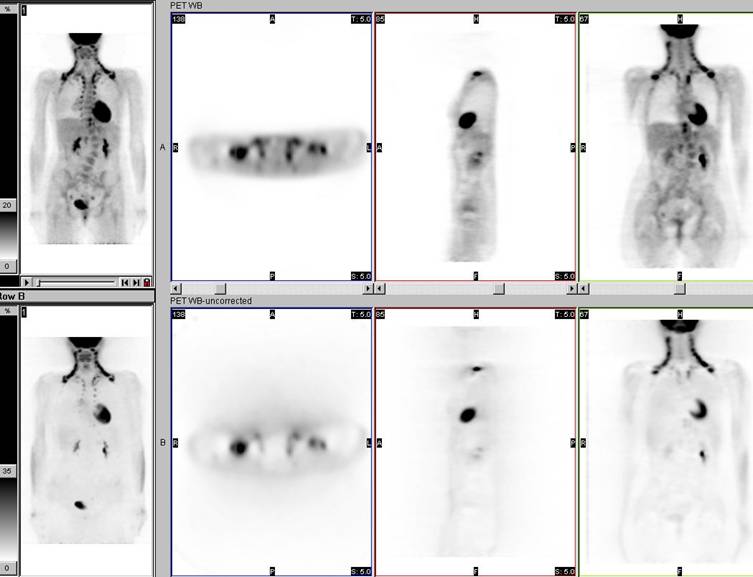

Brown fat activity on attenuation-corrected and non-attenuation-corrected PET data sets